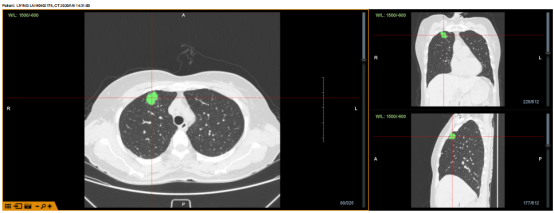

揭牌仪式后,在龙发主任开展手术演示。手术前,龙发主任与多位印度专家针对手术病例进行了谈论,制定了手术路径,其中包括一台气道内活检病例(Lungpoint),以及两台无明显气道相通病例(BTPNA)。隧道路径分别为36mm及34mm。均成功建立隧道,X光及超声小探头确认抵达病灶,耗时分别为20分钟、15分钟。

病例1:病灶位于右上叶前段,病灶大小约2cm,POE点位于RB3亚亚段,隧道长度36mm,使用FlexNeedle针穿刺,球囊扩张,再送入鞘管,于X光及超声下确认抵达病灶约耗时20份。

病例1

X光与超声确认抵达病灶